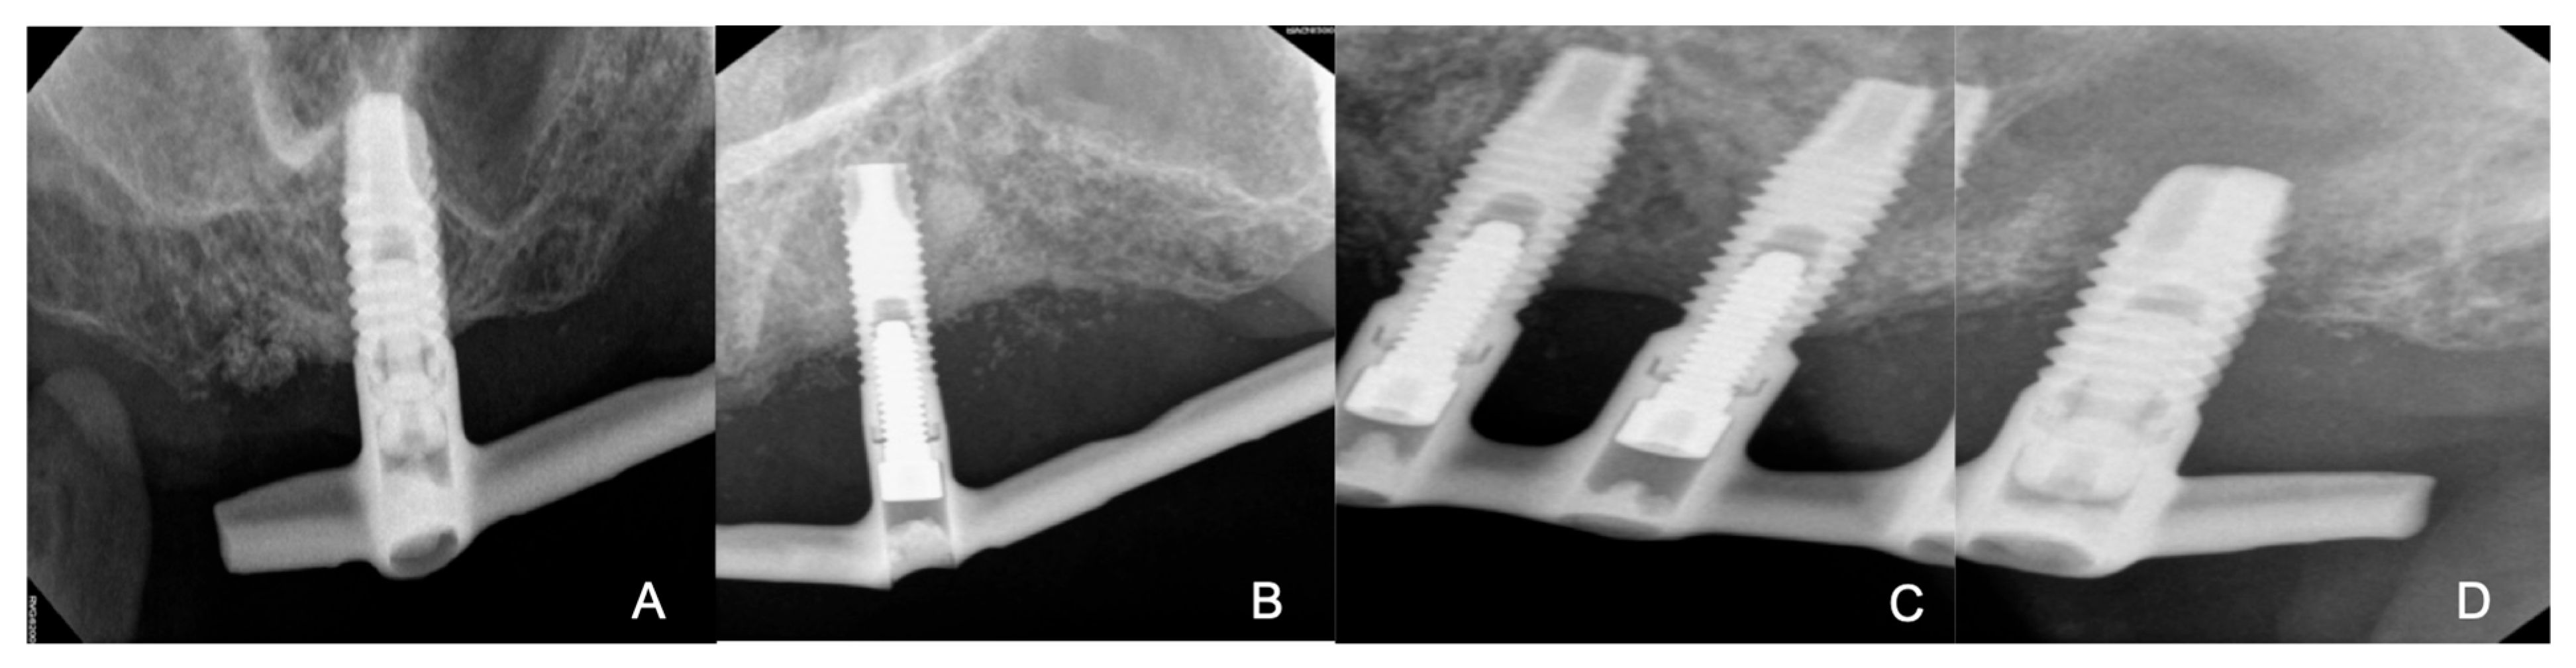

After a week, upon intraoral examination conducted in the Periodontics Department, radiographic images previously taken before the removal of the Hader bar attachment were reviewed. It was found that three implants with a probing depth (PD) of 4 mm showed bleeding without radiographic bone loss or suppuration (Figure 4A,C). One implant with a PD of 7 mm showed bleeding and suppuration in addition to radiographic bone loss greater than 2 mm (Figure 4B) and one implant with a PD of 11 m showed bleeding, suppuration, as well as mobility and bone loss around the entire perimeter of the implant (Figure 4D). This implant was chosen for extraction (Figure 4D) due to poor prognosis. The treatment of choice for the implant (Figure 4C) was implantoplasty.

Figure 4.

(A) Implant with good peri-implant health. (B) Implant with good peri-implant health. (C) Implant with peri-implantitis and exposed threads. (D) Implant with peri-implantitis and mobility.